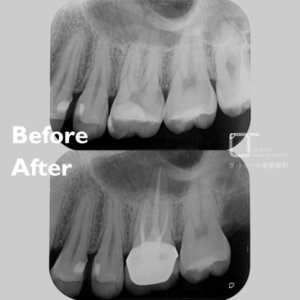

精密根管治療の治療例です。他院にて、神経の治療が必要になる可能性のある大きな虫歯があると指摘を受けたとのことでした。根管治療専門医による精密根管治療をご希望され、当院を受診されました。当院にて診査・診断を行い、専門医による根管治療を実施しました。

治療前と治療後の比較